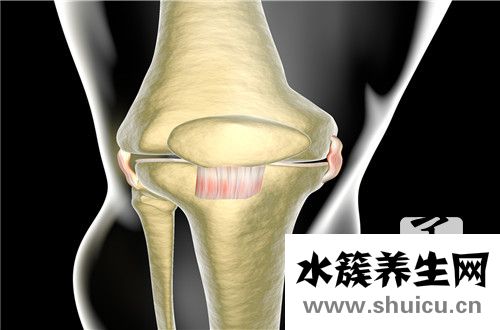

骨鹽(bonesalts)由無機鹽、又稱骨鹽有機基質(zhì)和骨細(xì)胞等組成。骨鹽增加骨的硬度,基質(zhì)決定骨的形狀及韌性,骨細(xì)胞在代謝中起主導(dǎo)作用。骨鹽分針形結(jié)晶和微顆粒結(jié)晶。

骨鹽占骨干重的65~70%,其主要成分為磷酸鈣,占84%,其它還有CaCO3占10%,檸檬酸鈣占2%,磷酸鎂占1%,和Na2HPO4占2%等。骨鹽約有60%以結(jié)晶的羥磷灰石(hydroxyapatite)形式存在,其余40%為無定形的CaHPO4。據(jù)認(rèn)為后者可以轉(zhuǎn)變?yōu)榍罢摺Au磷灰石[Ca10(PO4)6(OH)2]是微細(xì)的結(jié)晶,亦稱骨晶(bonecrystal)。每克骨鹽含有約1016個結(jié)晶,總的表面積可達(dá)100平方米,體液中其他離子如Ca2+、Mg2+、Na+、Cl-、HCO3-、F-,檸檬酸根等可吸附在羥磷灰石的晶格之間。骨晶性質(zhì)穩(wěn)定,不易解離,但在其表層進(jìn)行離子交換的速度較快。

骨中鎂離子占體內(nèi)鎂離子總量的50%,骨中鈉離子也占體內(nèi)鈉離子總量的35%,而且大部分鈉易于交換。所以骨骼不僅是身體的支持組織,也是貯存大量鈣、磷、鈉、鎂的器官,在維持體液電解質(zhì)濃度的穩(wěn)定性上具有重要作用。此外,骨鹽中的Ca2+還可與體液中的H+交換,當(dāng)體液中[H+]增多(酸中毒)時,由于Ca2+H+交換,可致骨鹽溶解。

骨基質(zhì)包括膠原和非膠原化合物。膠原約占90%以上。非膠原蛋白中含量較多的是骨鈣素(osteocalcin)和骨連接素(osteonectin)。骨鈣素為一種依賴維生素K的小分子酸性蛋白質(zhì),分子量約6000,其谷氨酸殘基在γ位羧化為γ-羧基谷氨酸,與羥磷灰石、Ca2+有很高親和力、骨連接素是附著于膠原的一種糖蛋白,易與羥磷石結(jié)合,可能作為骨鹽沉積的核心。

一般骨鹽量偏高容易造成骨質(zhì)疏松可能。目前,隨著非創(chuàng)傷性診斷技術(shù)的迅猛發(fā)展,骨鹽含量測定技術(shù)的敏感度逐步提高。大多數(shù)骨鹽含量測定技術(shù)適用于骨質(zhì)疏松,此時的骨質(zhì)密度只有數(shù)量上變化而沒有發(fā)生質(zhì)量方面改變,若人體骨骼出現(xiàn)腫瘤病變時,用骨鹽含量分析技術(shù)不太合適。